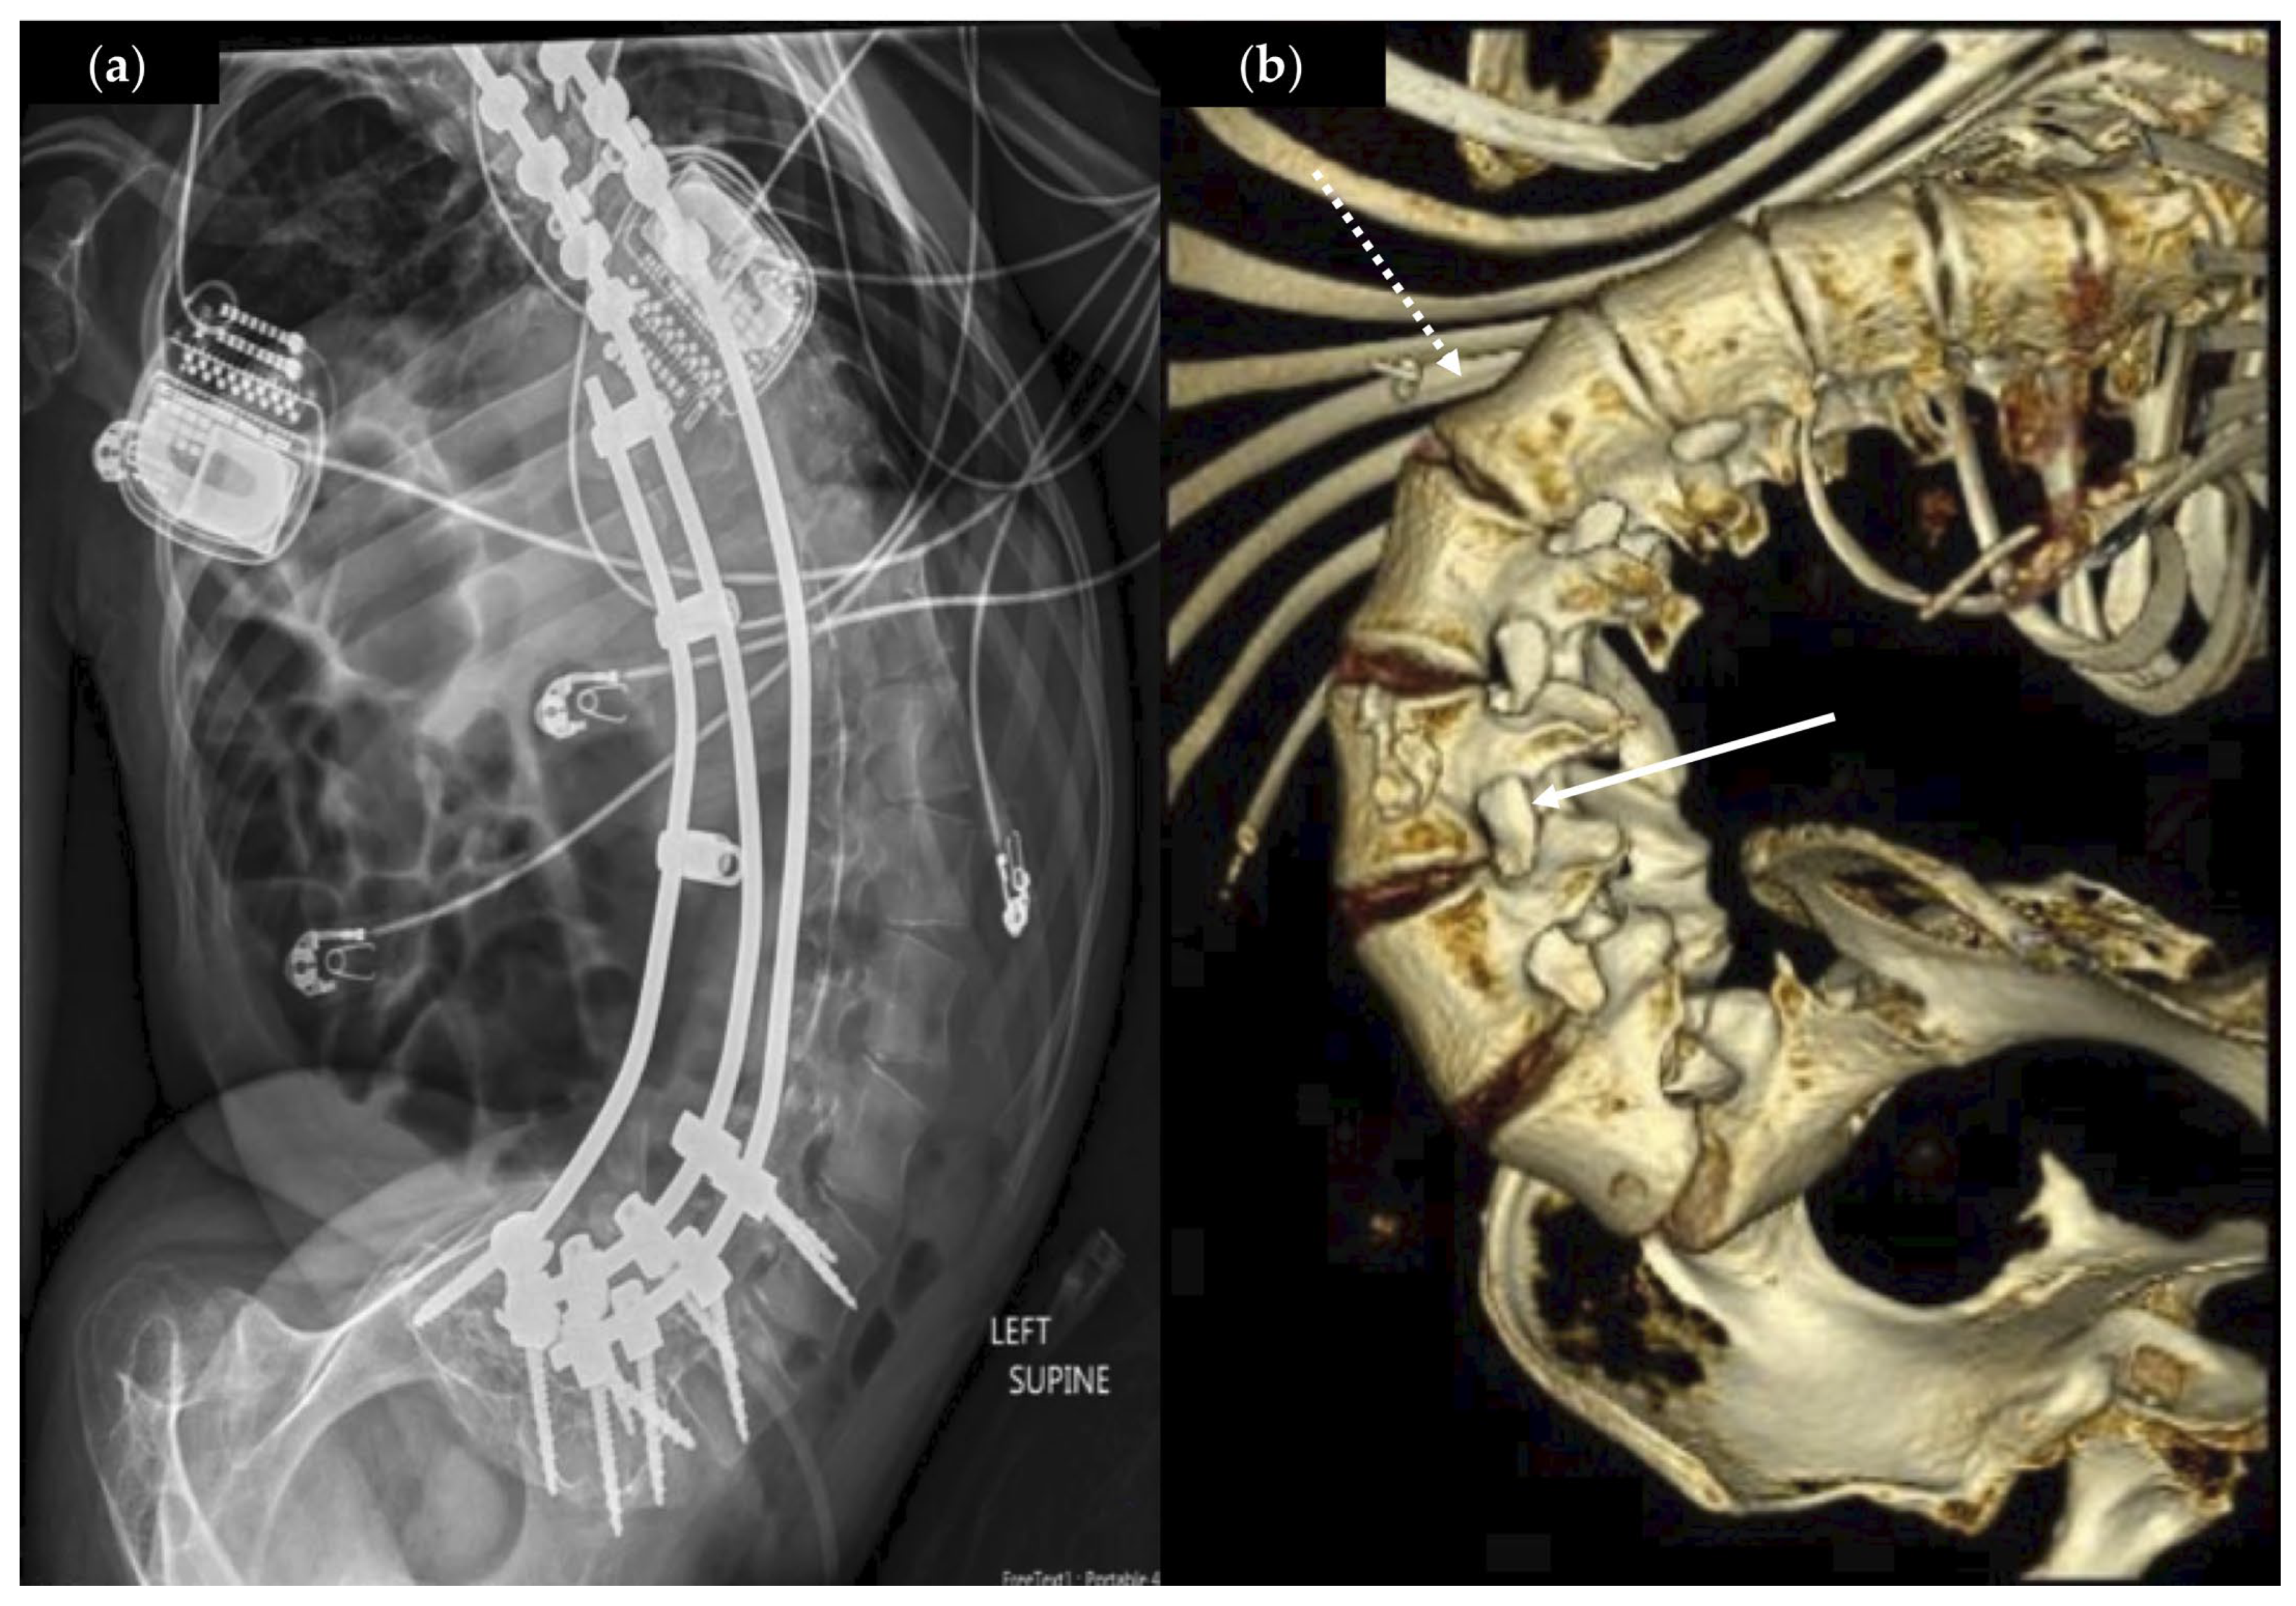

| 3 | 21, F | Hispanic | Quadriplegia, spastic | SMA2 | V | Y * | Y | 14.8 | T12-S1, 143 D ^ | +4, T12 | N | N |

| 3 | Bilateral L1-S1 | T12 | 209 | 50 | 3 | 3 | Mild neuropathic pain | Improved ROM |